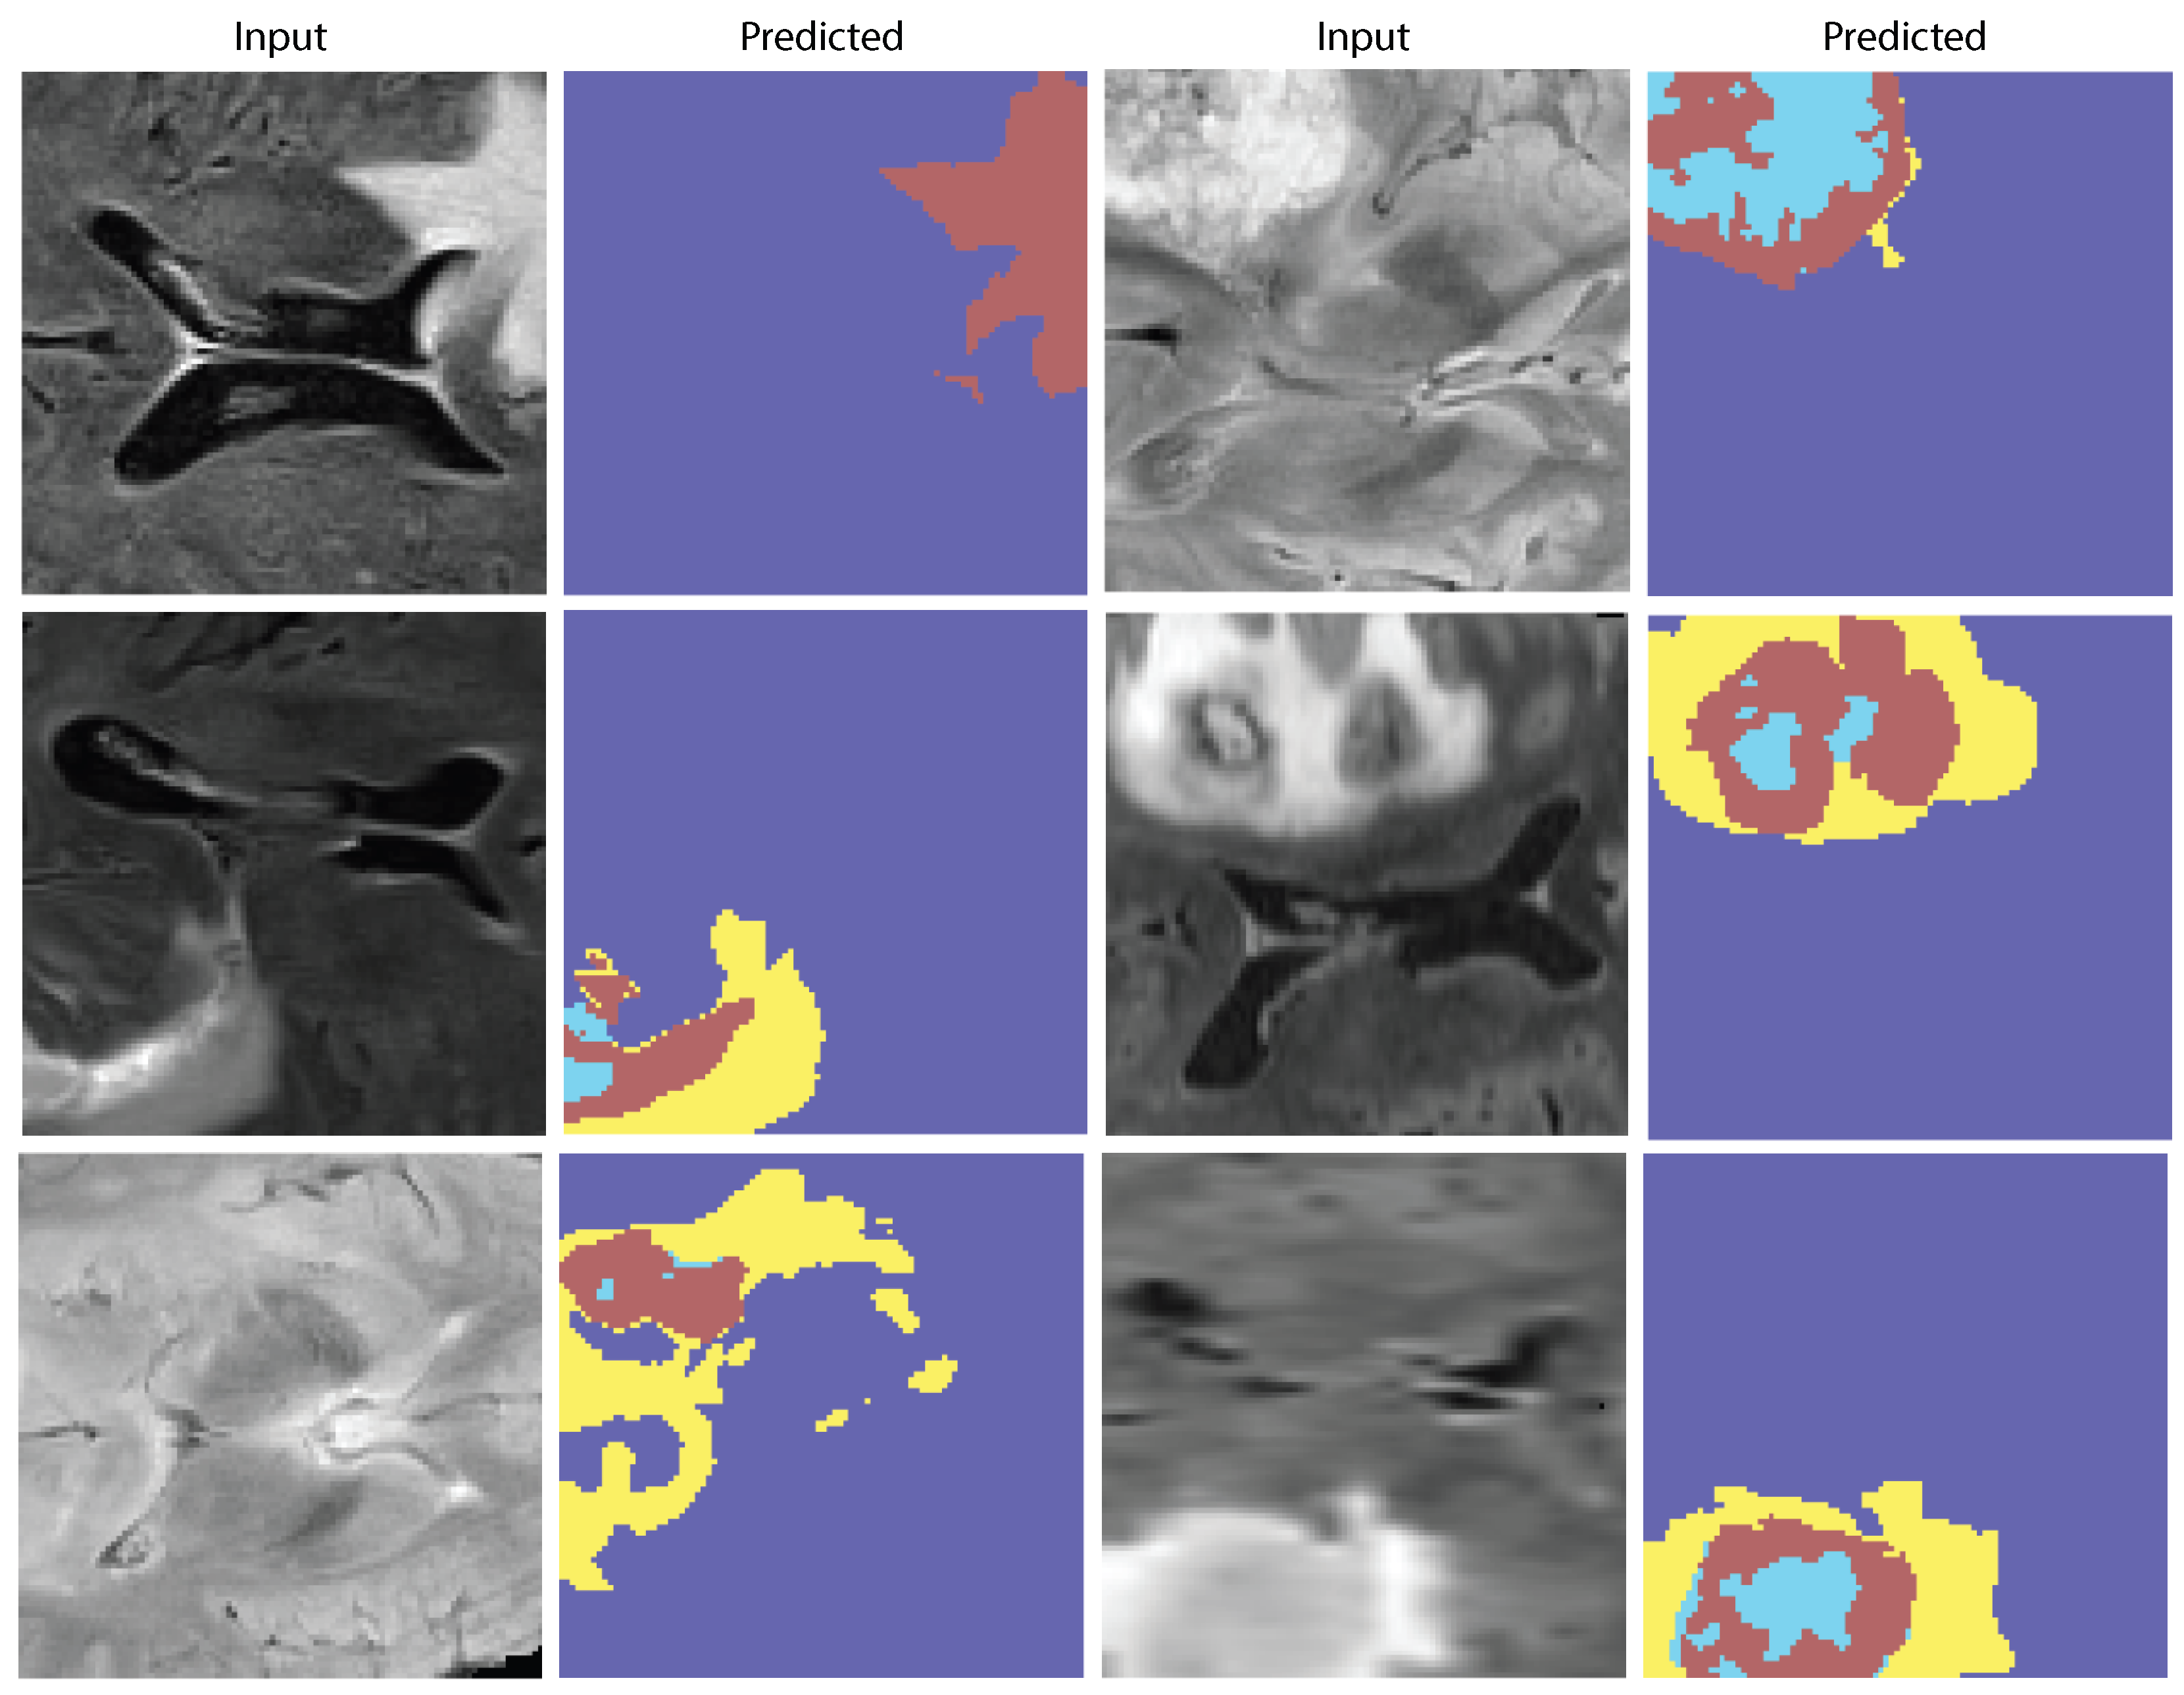

Figure 9. Qualitative results. Representative FLAIR slices with ground-truth masks and AVLT predictions; salient tumor subregions are captured consistently with the reference annotations.